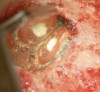

Figure 5b  This procedural error may have delayed the progress of therapy or even made it impossible to thoroughly clean and shape the canal terminus. Root-end surgery was performed to enucleate the periapical pathology and debride previously uncleaned parts of the canals. On the apically resected root surface, an uncleaned portion of 1 canal and an isthmus connecting the 2 main canals became visible under high magnification (Figure 5B), which were prepared to 1 retrocavity using ultrasonic tips (Figure 5C) and filled with MTA (Figure 5D).

Figure 5b